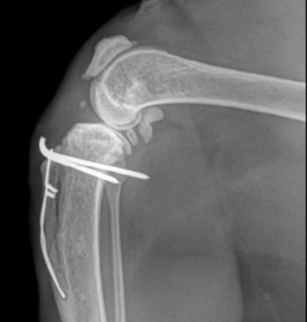

고양이 무릎 관절낭 내부에 양성 골종양이 생긴 증례이다.

딱 봐도 겁먹을 정도로 거대한 뼈조각 증식이 보인다.